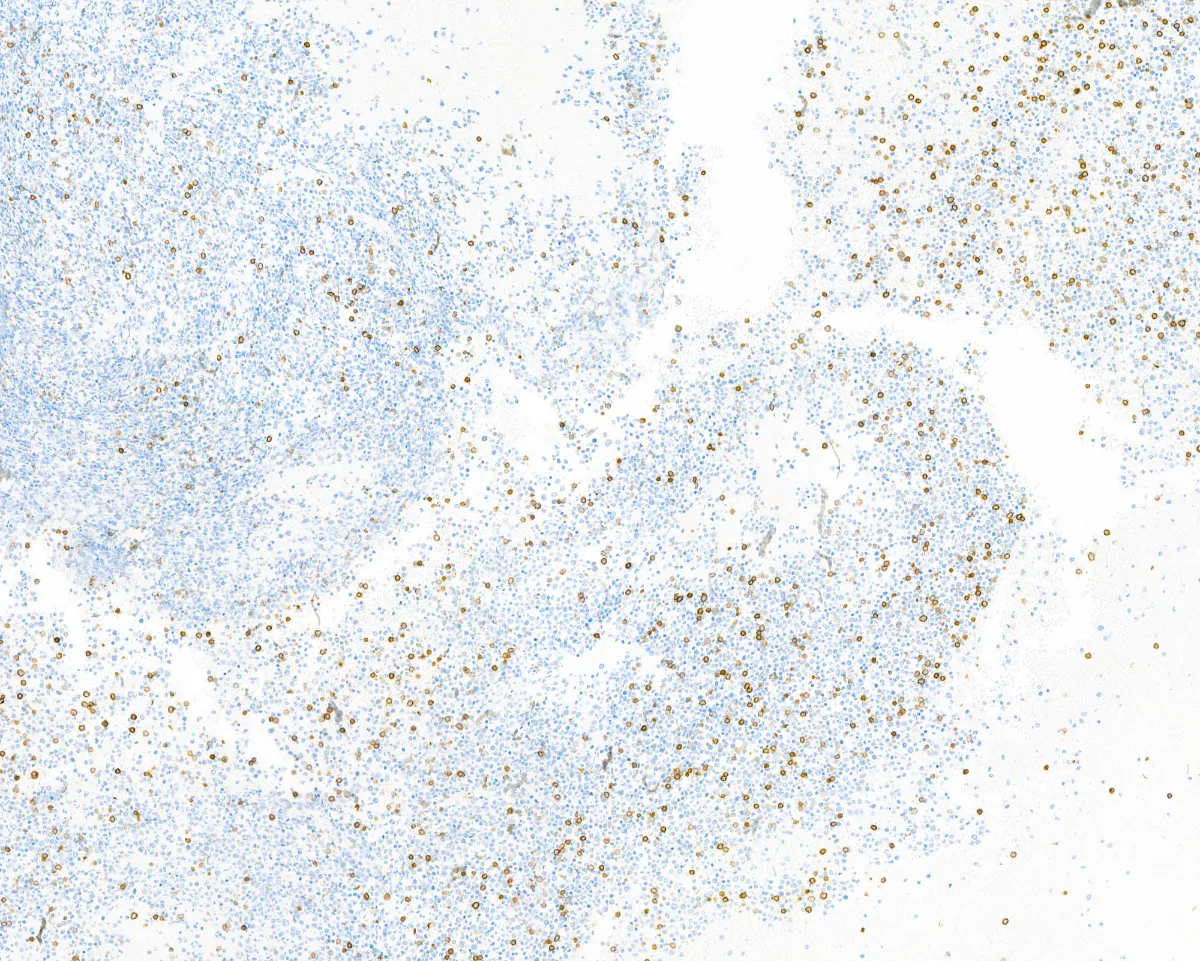

Imágenes:

CD3

- Está compuesto por sábanas de células de tamaño intermedio de origen mieloide, positivas para CD34 y MPO (PMID: 39328673).

- El estudio inmunohistoquímico para detectar marcadores de serie monocítica, tales como CD68, CD163 o MPO puede ayudar a la distinción entre el sarcoma mieloide intracraneal de otros procesos neoplásicos o reactivos (PMID: 40951121).